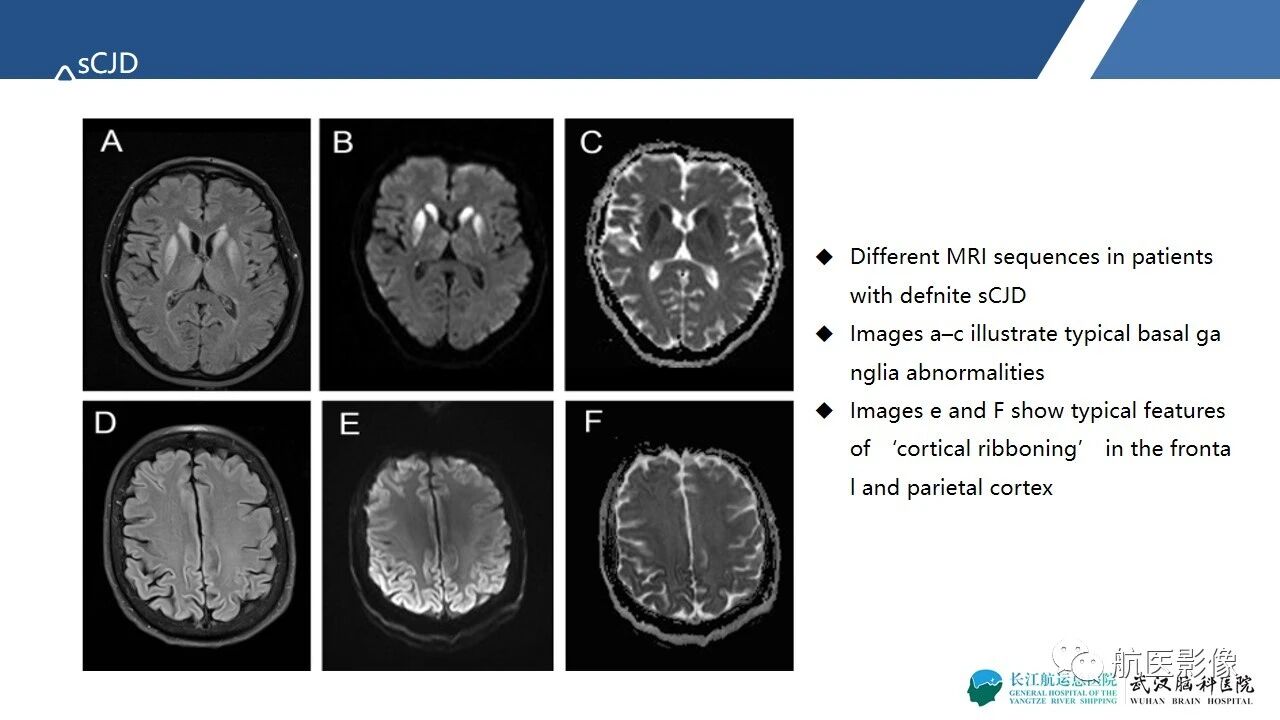

基底节区、丘脑对称性病变影像表现